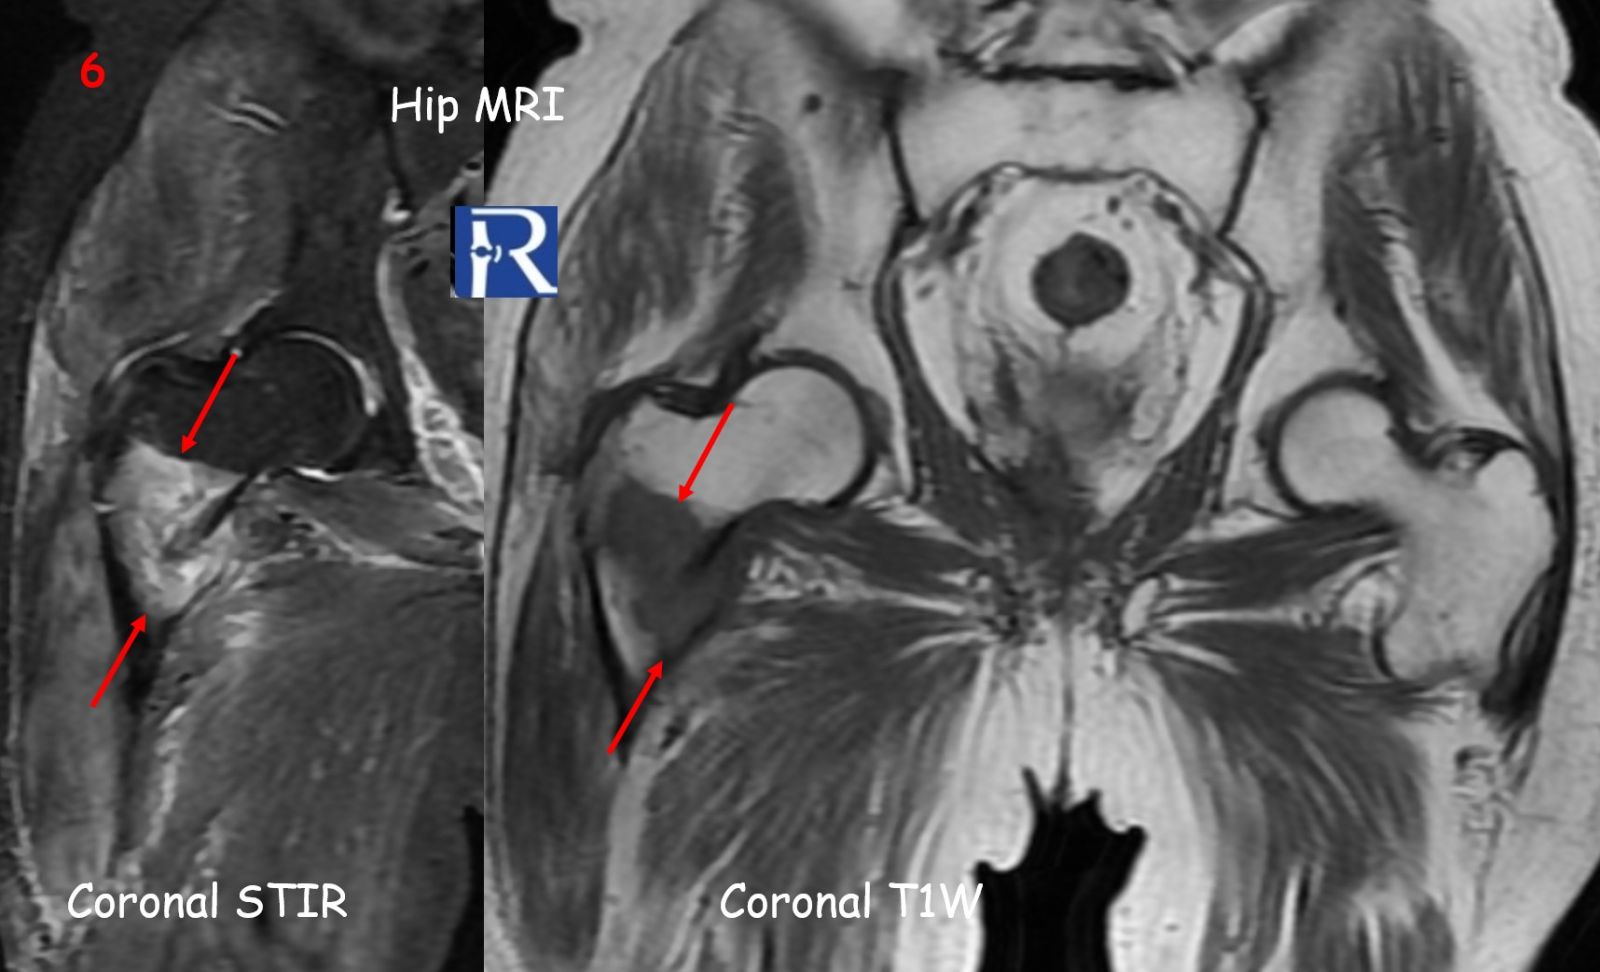

MRI (Figures 5–6) performed two weeks later revealed progression to a pathologic fracture and extension of a hypointense soft-tissue lesion into the intertrochanteric area, compatible with metastatic infiltration.

⚪ White arrows → Avulsed bone fragment

???? Red arrows → Tumoral infiltration margins